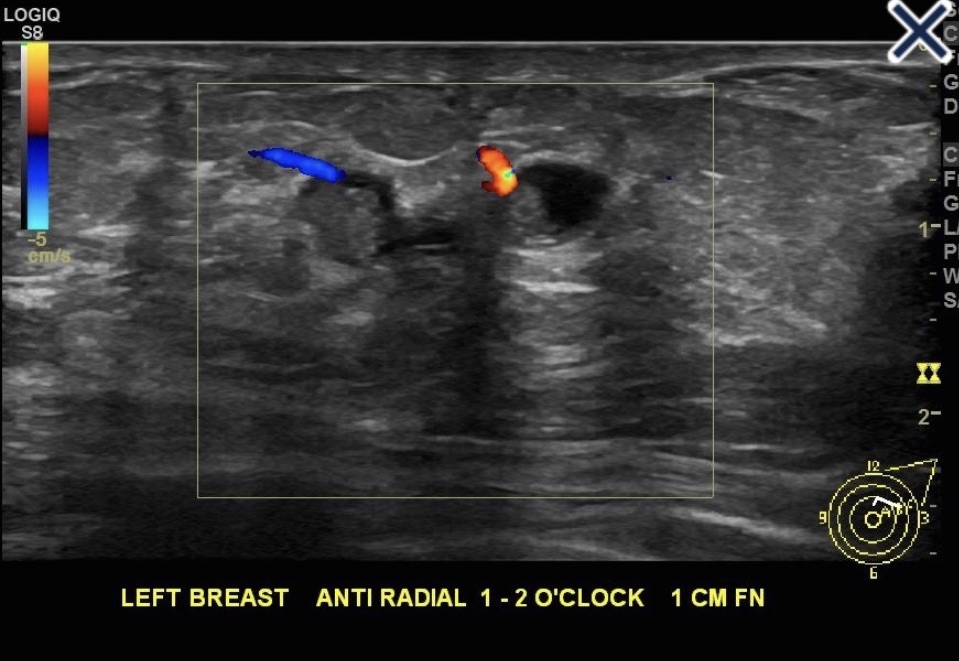

• These highly vascular lesions:

• A vascular stalk may be demonstrated on color Doppler scanning while multiple feeding vessels may be seen when imaging malignant papillary lesions

• When papillary lesions infarct, the vascular stalk will not be demonstrated

• The mural nodule caused by papillary apocrine metaplasia also would not extend into the duct as the papillary lesion shown in the image does